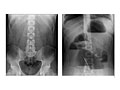

Abdominal X-Ray

An abdominal X-ray is a picture of structures and organs in the belly (abdomen). This includes the stomach, liver, spleen, and large and small intestines. It also includes the diaphragm, which is the muscle that separates the chest and belly areas. Often two X-rays will be taken from different positions. If the test is being done to look for certain problems of the kidneys or bladder, it is often called a KUB (for kidneys, ureters, and bladder).

Often two pictures are taken: one while you are lying down (supine) and the other one while you are standing (erect view). If you are not able to stand, the X-ray may be taken while you lie on your side with your arm over your head.